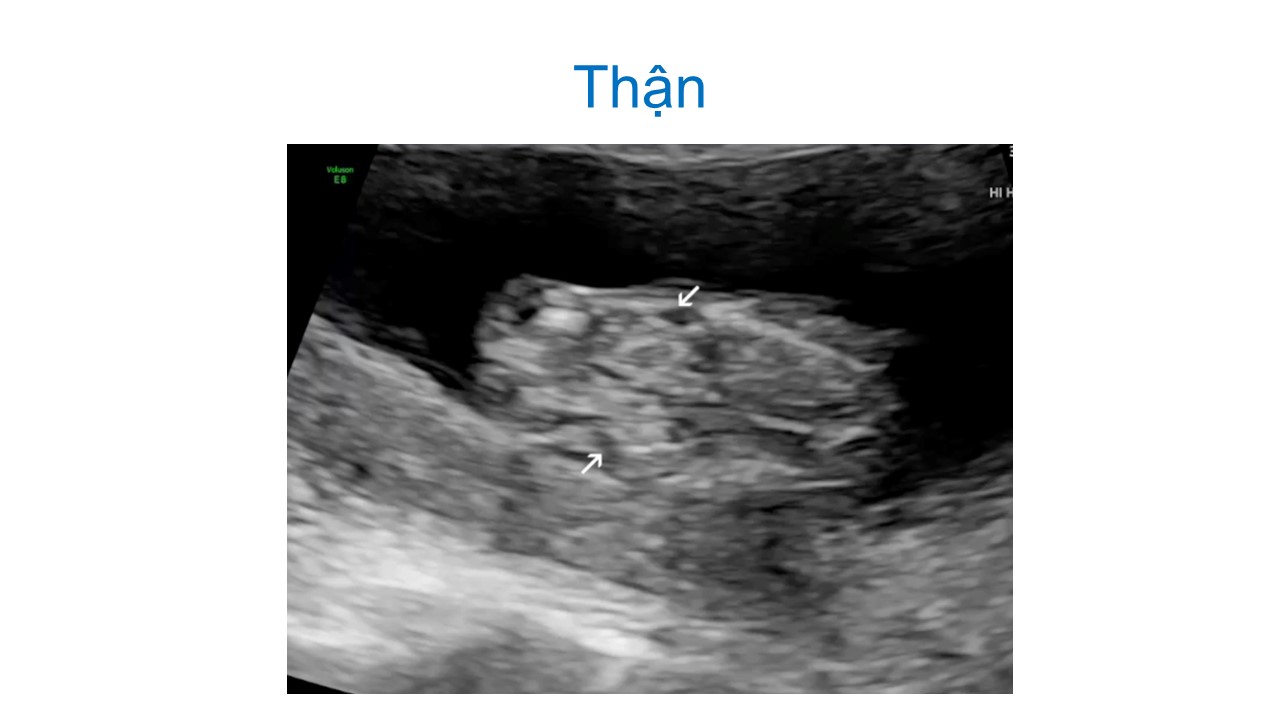

Siêu âm hình thai học quý I

Từ khóa: Siêu âm hình thai học quý I